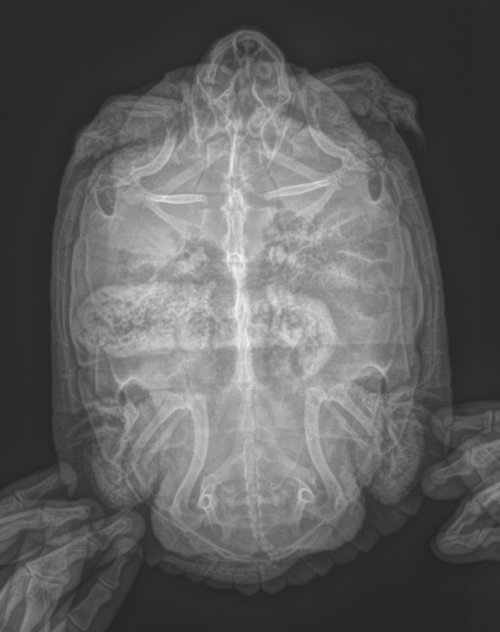

Для начала надо сделать цифровой рентген. В каких проекциях надо сделать, чтобы определить причины ? Или лучше все 3. С живота, профиль и сверху (черепашка головой вверх). И какие есть нюансы, чтобы врачу сообщить.

в идеале в 3х проекциях, настройки обычно  67кВ на 2мА/сек, также допустимо 50кВ на 6-8мА/сек

Похоже в моем случае все куда хуже и серьёзнее (((

Из того, что я вижу - у черепахи каловый завал или вообще непроходимость и уменьшен объем лёгких. Создать для Вас тему? Может помогут найти хорошего очного врача в Туле.